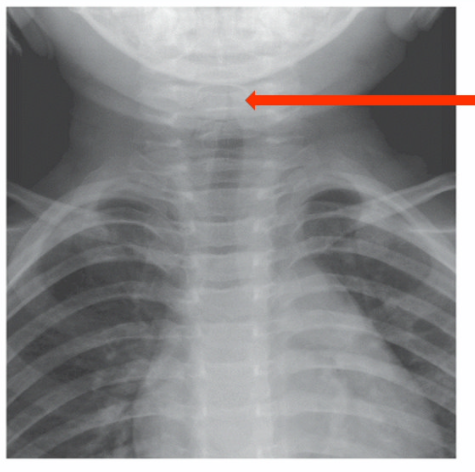

describe the image